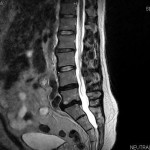

An MRI scan while sitting on a Back App

An MRI Scan While Sitting on the Back AppI recently-…-